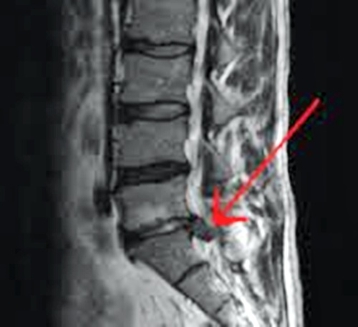

허리 디스크로 인해서 통증이 심한 분들은 영상의학적인 검사를 통해서 디스크가 터져서 아픈지 아닌지만 확인을 하려고 합니다.

허리디스크의 문제가 요추 자체의 불안정성에서도 올 수 있지만 더 나아가 고관절, 천장관절, 발목, 경추 등 다른 체형 불균형의 문제에서 기인할 수 있는데 일반적인 검사를 통해서는 이러한 문제점을 찾을 수 없습니다.

허리디스크가 터진 것을 확인 = CT, MRI 검사

허리디스크가 "왜" 터졌는지 확인 = 복합적인 검사, 한의학적 시각 필요